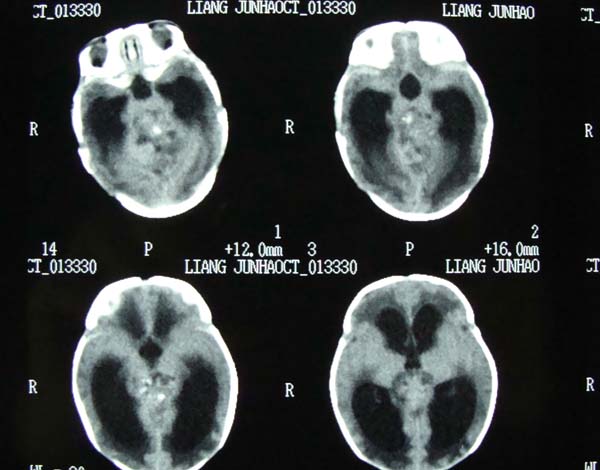

病史,xxx,男,10个月,前囟饱满.呕吐.

考虑第四脑室室管膜瘤并阻塞性脑积水。

小脑蚓部髓母细胞瘤?第四脑室室管膜瘤?合并重度阻塞性脑积水。

考虑四脑室脉络丛乳头状瘤或室管膜瘤并阻塞性脑积水

考虑四脑室室管膜瘤伴阻塞性炎症。

考虑第四脑室室管膜瘤并阻塞性脑积水

考虑第四脑室室管膜瘤或髓母细胞瘤并阻塞性脑积水。

诊断:髓母细胞瘤并梗阻性脑积水.

依椐:颅后窝中线小脑蚓部占位,病灶内呈混杂密度,四脑室受压前移,第三脑室及侧脑室扩张.